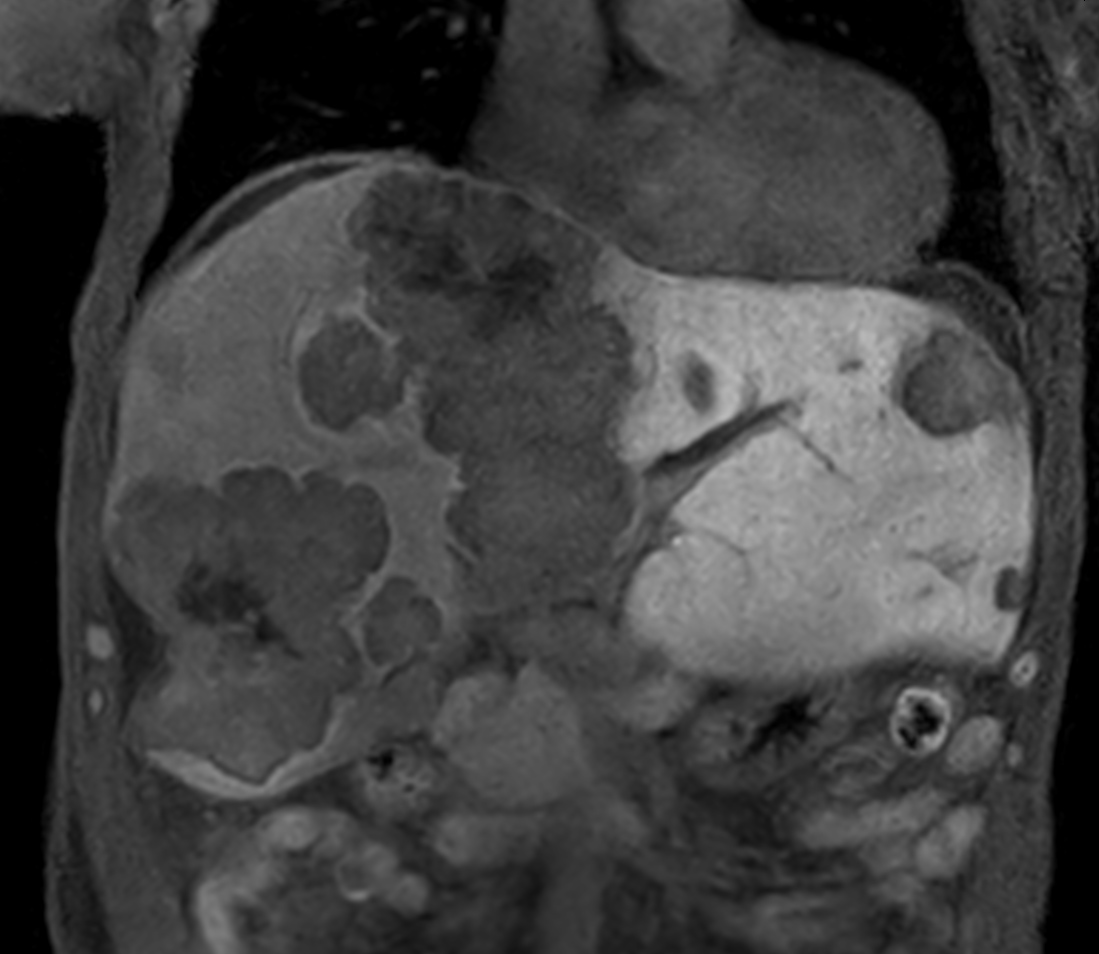

Patient with liver metastasis. The ExamCard includes techniques for efficient fat-free imaging over large field-of-views (mDIXON XD), a procedure for non-invasive liver fat quantification (mDIXON Quant), a multi-phase contrast-enhanced sequence (4D FreeBreathing) to improve imaging confidence and Compressed SENSE to accelerate the entire exam.

T1w mDIXON XD FFE Compressed SENSE